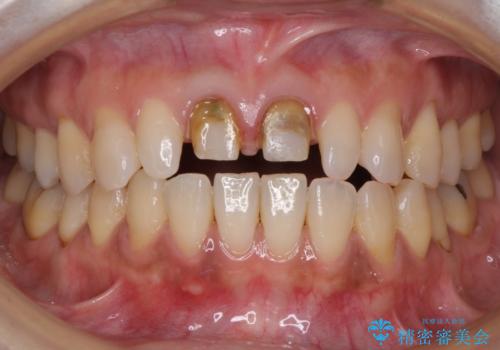

前歯をメタルフリーに 根管治療で不安を取り除いてから

- 他院で奥歯に虫歯があると言われて、ご来院された患者様です。チェックしたところ、奥歯に虫歯は認められませんでした。

前歯に違和感や根尖病巣(根の先に細菌が溜まっている)が認められたため、治療をご提案しました。

セラミック治療と根管治療を行いました。

患者様は、もともと奥歯の虫歯を心配してご来院されましたが、前歯に問題が見つかりました。

金属を使用したメタルボンドクラウンが入っていたため、いつかオールセラミックにしたいときに根管治療も行ったほうが良いとご提案し、今回行いました。

歯と歯肉の境目の色は、歯自体が黒くなっている場合、完全にカバーすることは難しいです。